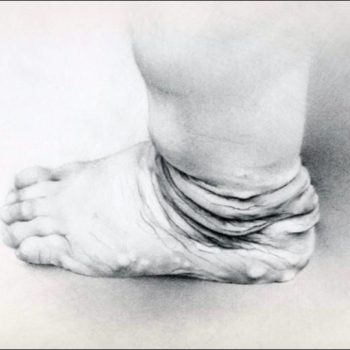

Fallen Socks Sign of Lax Skin – Dermatosparaxis

Please click to enlarge.

Note what signs you see.

I (W. Wertelecki, M.D.) see the photograph of the subject illustrated in the Gallery.

PERSPECTIVE: Please, see the principles of identification of “new” human disorders and related video of this patient.